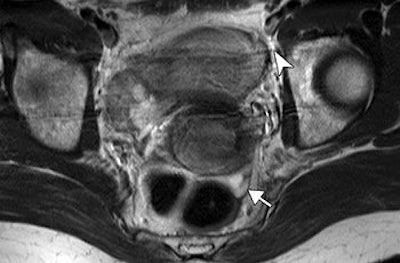

| Same patient as above. Gadolinium-enhanced axial T1-weighted turbo spin-echo sequence image (175/4.2; echo-train length, 3) shows homogeneous enhancement of left internal iliac lymph node (arrow). Histopathology showed one positive node in left internal iliac and obturator area of four nodes sampled. Choi HJ, Kim SH, Seo S, Kang S, Lee S, Kim JY, Kim YH, Lee JS, Chung HH, Lee JH Park SY. "MRI for Pretreatment Lymph Node Staging in Uterine Cervical Cancer" (AJR 2006; 187:W538-W543). |

Other reliable indicators of lymph node status on MR were a lobulated or spiculated border (21% sensitivity and 46.4% positive predictive value). These margins could be caused by a "desmoplastic reaction or tumor infiltration into the perinodal fat." However, heterogeneous enhancement patterns were not as useful for distinguishing metastatic from nonmetastatic lesions, they added.

The group ultimately concluded that despite MRI's low sensitivity, size and margin were useful criteria for predicting lymph node metastasis in cervical cancer patients. But they did caution that size and margins can overlap in metastatic and nonmetastatic lesions.